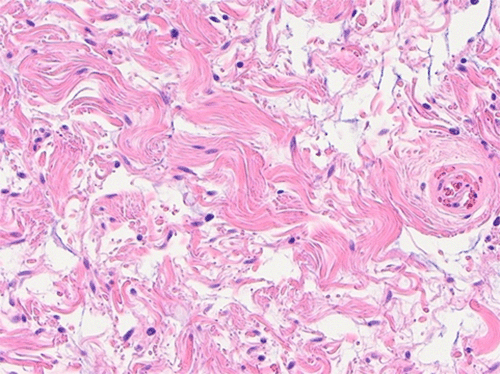

The final pathology report was consistent with a pseudoangiomatous spindle cell lipoma. Grossly, the soft tissue mass was red to yellow in color, well-circumscribed, and measured 19.0 × 9.6 × 3.3 cm. Upon palpation, the mass appears gelatinous with central firm nodular areas. Serial sectioning revealed a pink-tan heterogenous and multilobulated cut surface with areas of myxoid change and cystic degeneration. Focal areas of hemorrhage were also noted. The impression of firm pink to tan nodules centrally was confirmed (Figure 3).

Figure 3. Surgical Pathology. Published With Permission

C) 10x: Ropey collagen was present diffusely throughout tumor, distinct pathologic finding in spindle cell lipomas

D) 20x: Bland-appearing spindle cells in background of ropey collagen